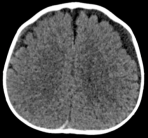

Nowhere in the police investigation transcripts does it suggest that doctors considered Johan had a brain injury and retinal hemorrhaging due to low blood-oxygen levels and high carbon dioxide pressure, problems that may result from faulty intubation.

The retinal hemorrhages in Johan’s eyes were widespread and multi-layered, the kind that child abuse pediatricians insist do not result from short falls or lack of oxygen to the brain. So were the hemorrhages in the eyes of the toddler in the care of René Bailey, who said the little girl had fallen off a chair—Bailey’s murder conviction was vacated in December. Doctors also pointed to extensive retinal hemorrhages when diagnosing shaking injuries in the cases of exonerated babysitters Jennifer Del Prete and Audrey Edmunds and exonerated father Drayton Witt, and in an exasperating case local to me in which paramedics pulled a rubber band from the child’s throat during resuscitation and the only physical evidence of abuse was the triad. It seems to me that the world now offers quite a few examples of extensive retinal hemorrhages from plausible, non-abusive accidents and medical conditions.

When I started researching shaken baby theory more than 15 years ago, I routinely read in trial transcripts that doctors considered the presence of retinal hemorrhages a sure sign of child abuse, but since then the situation has grown more complicated. When researchers started looking systematically, they rediscovered that retinal hemorrhages have a long list of non-traumatic causes, including diabetes, anemia, bleeding disorders, increased intracranial pressure, increased intrathoracic pressure, and certain types of infections. A startling one quarter of neonates born spontaneously arrive with retinal hemorrhages, more in deliveries that involve instruments. In light of this new understanding, child abuse experts now recognize other causes of retinal hemorrhages but insist that most of them result in only a few small hemorrhages near the optic nerve, not in widespread, multi-layer hemorrhages, which they continue to interpret as evidence of whiplash shaking.I don’t know how we will move forward, but I welcome the growing chorus of voices in the journals, in the press, and in the courtroom, who demonstrate through their work and their testimony that the Open Letter on Shaken Baby is representing the situation correctly in its message to the courts: